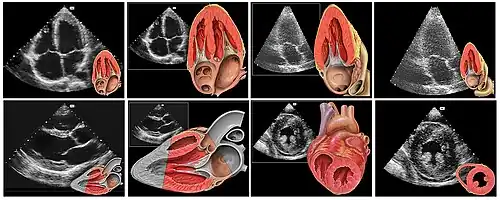

Le cœur est un organe intra thoracique, entouré d'air (les poumons) et d'os (les côtes). Ces deux dernières structures ne laissent pas transmettre les ultrasons, rendant l'examen plus complexe. On se sert ainsi d'un nombre limité de « fenêtres » anatomiques, lieux où le cœur peut être visualisé par l'échocardiographie, sans interposition aérienne ou osseuse.

Le patient est installé torse nu, allongé sur le côté gauche (décubitus latéral gauche). Il n'a pas besoin d'être à jeun. Éventuellement, trois électrodes sont collées afin de disposer d'un tracé ECG simultané. L'examinateur, suivant son habitude, est à la droite ou la gauche du patient. Il applique la sonde d'échographie recouverte d'un gel (permettant un meilleur passage des ultrasons à travers la peau) sur la peau de ce dernier suivant différentes positions constituant les fenètres d'échographie dont les principales sont :

- « Voie para sternale gauche » : entre la troisième et la quatrième (voire entre la quatrième et la cinquième) côte, juste à gauche du sternum ;

- « Voie apicale », partie inférieure gauche du sternum, là où est perçu le mieux à la palpation le battement cardiaque (« choc de pointe ») ;

- « Voie sous costale ou sous xyphoïdienne », dans le creux en dessous de la xiphoïde du sternum.

Les quatre valves cardiaques (mitrale, tricuspide, aortique et pulmonaire) sont bien visualisées : on analyse la mobilité des feuillets, leur épaisseur. Le doppler permet de calculer la surface fonctionnelle (diminuée en cas de rétrécissement d'une valve) ainsi que la présence et l'importance d'une fuite.

Échographie tridimensionnelle

Par le biais d'un capteur non plus linéaire, mais matriciel, une imagerie tridimensionnelle directe est possible. Cette technique relativement nouvelle (la sonde matricielle étant disponible à relativement grande échelle depuis 2002), est en cours d'évaluation.